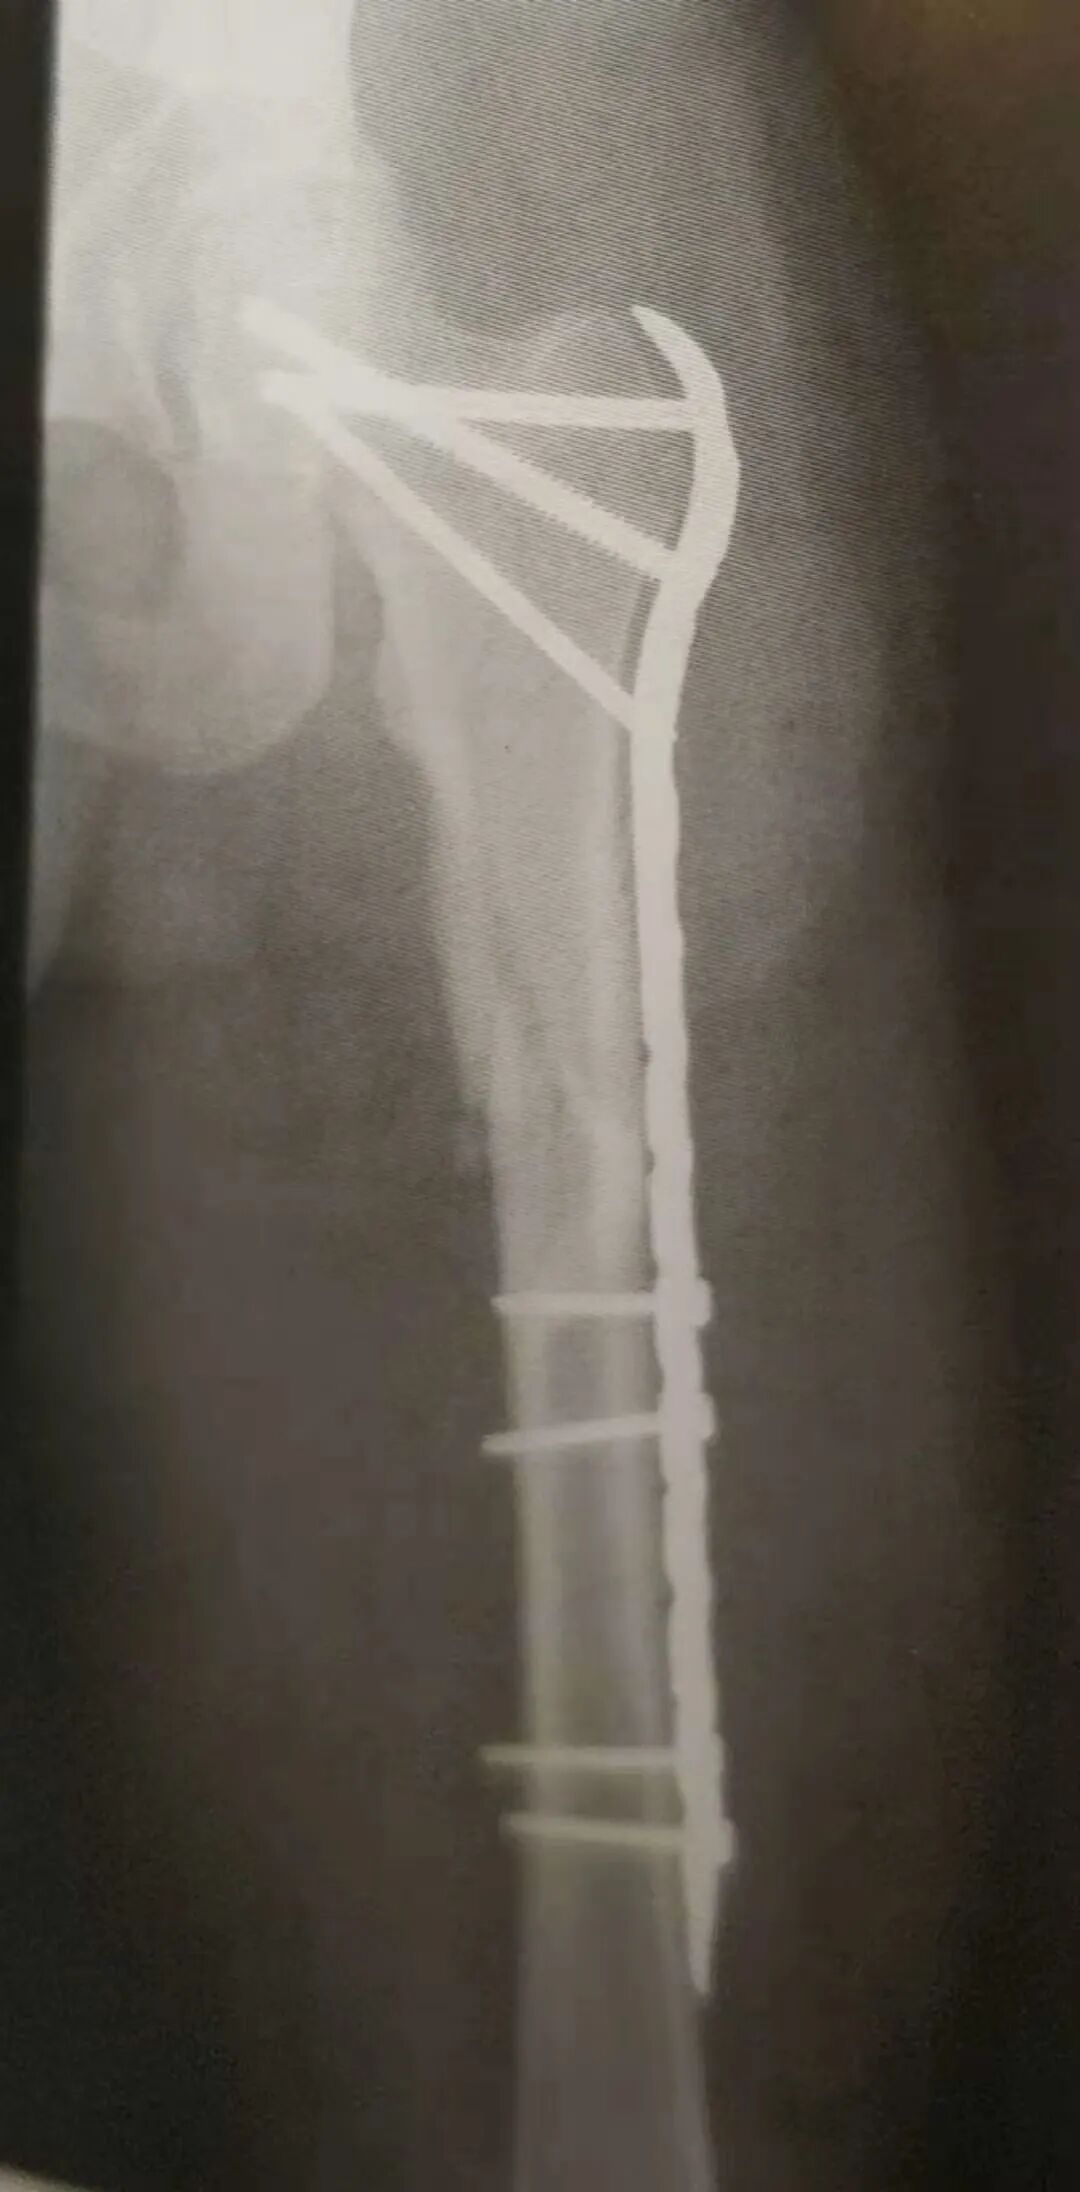

▲ 复杂股骨近端骨折累及转子下通过股骨近端锁定接骨板获得固定

9)股骨颈基底部骨折或者转子间骨折延伸到转子下的部分需要进行加压。加压可通过以下方法之一实现:

• 金属板(不是固定角度金属板)外拉力螺钉固定。

• 在股骨近端锁定接骨板上的结合空内使用拉力螺钉技术固定。

• 股骨近端锁定板上的拉力螺钉仅用作临时固定。待拉力螺钉周围的钉孔都完成锁定固定后,骨折端的拉力已经获得维持。不再需要拉力螺钉,因此,在完成全部锁定螺钉固定后,拉力螺钉取出或者更换为锁定螺钉。

• 拉力螺钉作为固定角度内植物(DCS,SHS)的一部分。需要注意滑动髋螺钉必须要与转子外侧接骨板配合使用,否则滑动髋螺钉没有滑动距离的限制,会导致股骨内移。

▲ DCS提供的长的工作长度以及手术切口